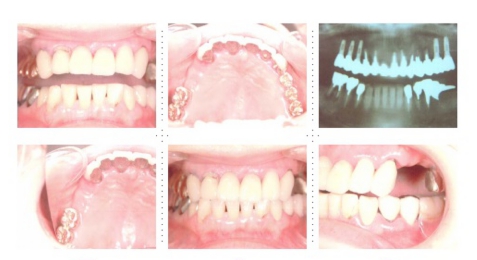

症例2

62才 女性

上顎は総義歯、下顎はブリッジと局部床義歯が装着。義歯は違和感があり、食事も不便を感じ、審美的にも人前にでるのが苦痛に感じていました。この状態を打破するためにも、「インプラント治療に自分の人生を賭けてみたい」という覚悟で来院されました。インプラント手術に対する恐怖心も強くお持ちでした。このような骨幅が狭いケースでは、X線撮影と共にCT撮影による画像診断とインプラント埋入シミュレーションが重要です。

下顎は両側犬歯を残し、他は抜歯。インプラント7本埋入。 上顎はインプラント8本埋入。 インプラント手術を受けられる患者さんは、前の晩眠れない程の不安感、恐怖心を持って来院されます。実際には麻酔注射は痛みを感じず、インプラント手術も痛みも無く、短時間(1本平均3分)で終わるという、当院独自のテクニックにより、2回目からのインプラント手術は気楽になるようです。 前歯は仮歯の段階で患者さん、歯科医、技工士の三者で、審美性・機能性の面から10回以上形態修正を繰り返し検討した後、上・下顎共に前歯・小臼歯はセラミック(MB)クラウン、大臼歯はゴールドクラウンを装着。ご本人とご家族の方にも、「アンチエイジングには、審美インプラント治療が一番効果あり」と大変喜んで頂きました。